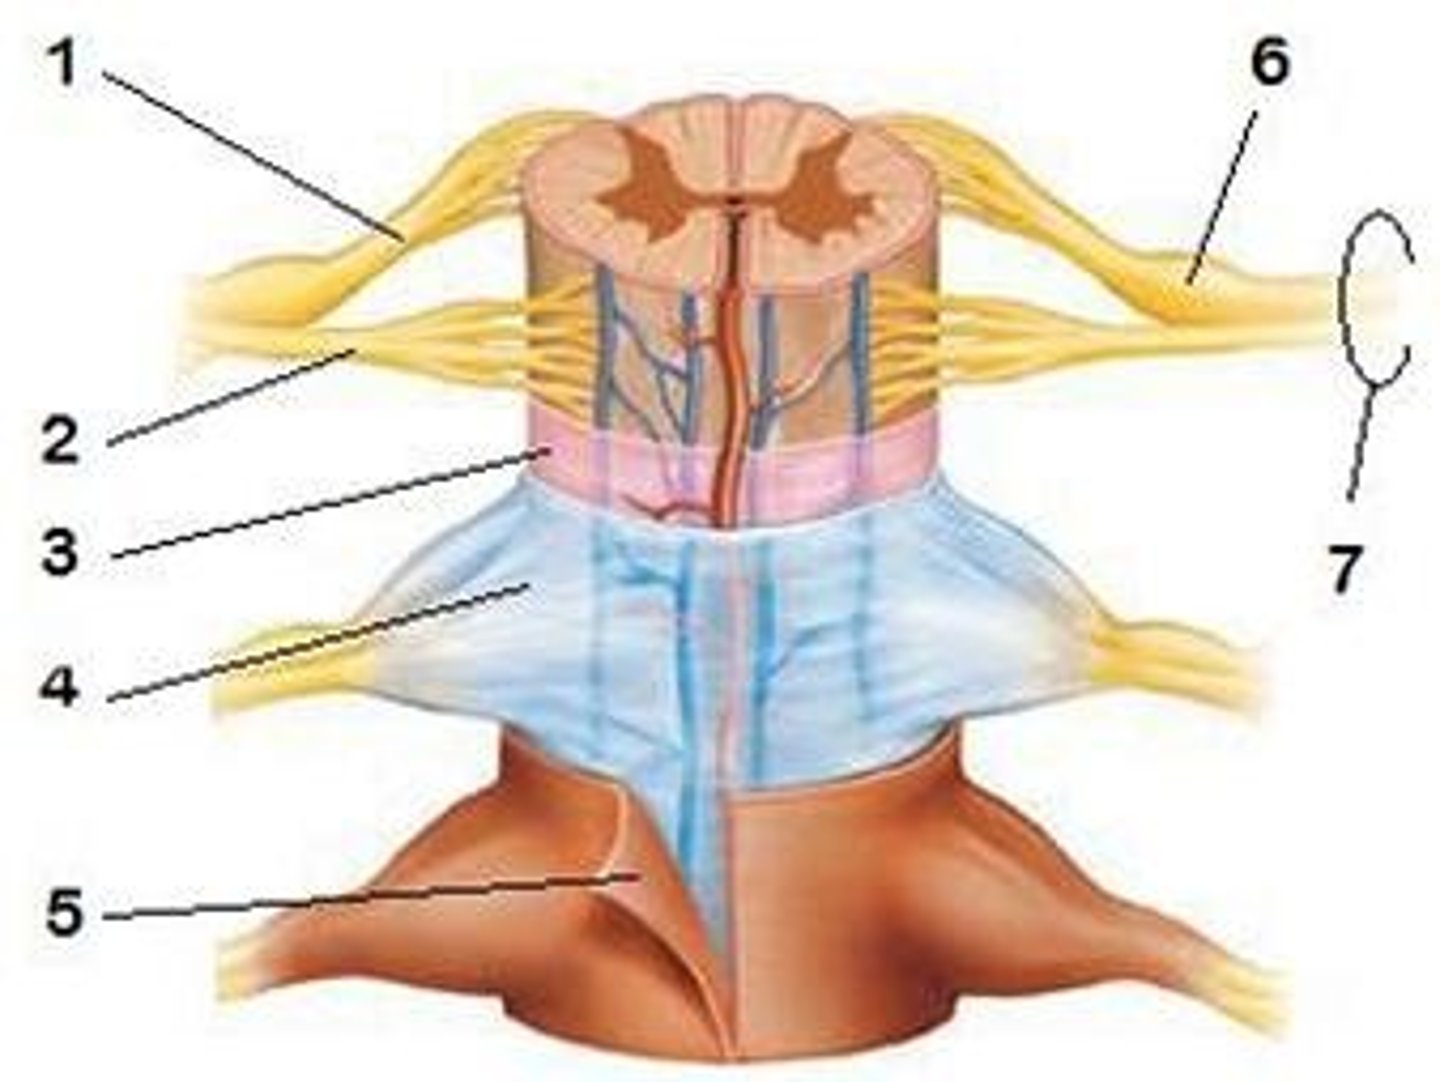

31 pairs of nerves arising from the spinal cord; letter abbreviation for region of spine they originate from; forms where the anterior and posterior roots join; mixed nerves (contain sensory and motor fibers)

posterior (dorsal) rootlets

merge to form a root

posterior (dorsal) root

contains sensory axons

posterior (dorsal) root ganglion

contains cell bodies of sensory neurons

true spinal nerve

anterior root

contains motor axons

ramus

points where the spinal nerve branches; occurs away from the spinal cord

posterior (dorsal) ramus

innervates the muscles and joints in that region of the spine and the skin of the back

anterior (ventral) ramus

•Splits into multiple other branches

•At different levels, this ramus innervates anterior and lateral trunk, upper limb, lower limb

•Participates in plexuses

spinal meninges

dura mater, arachnoid mater, pia mater (PAD to protect the spinal cord from deep to superficial)

dura mater (spinal cord)

thick, outermost layer of the meninges; 5 on image

arachnoid mater (spinal cord)

middle weblike layer of the meninges; 4 on image

pia mater (spinal cord)

thin, delicate inner membrane of the meninges; 3 on image